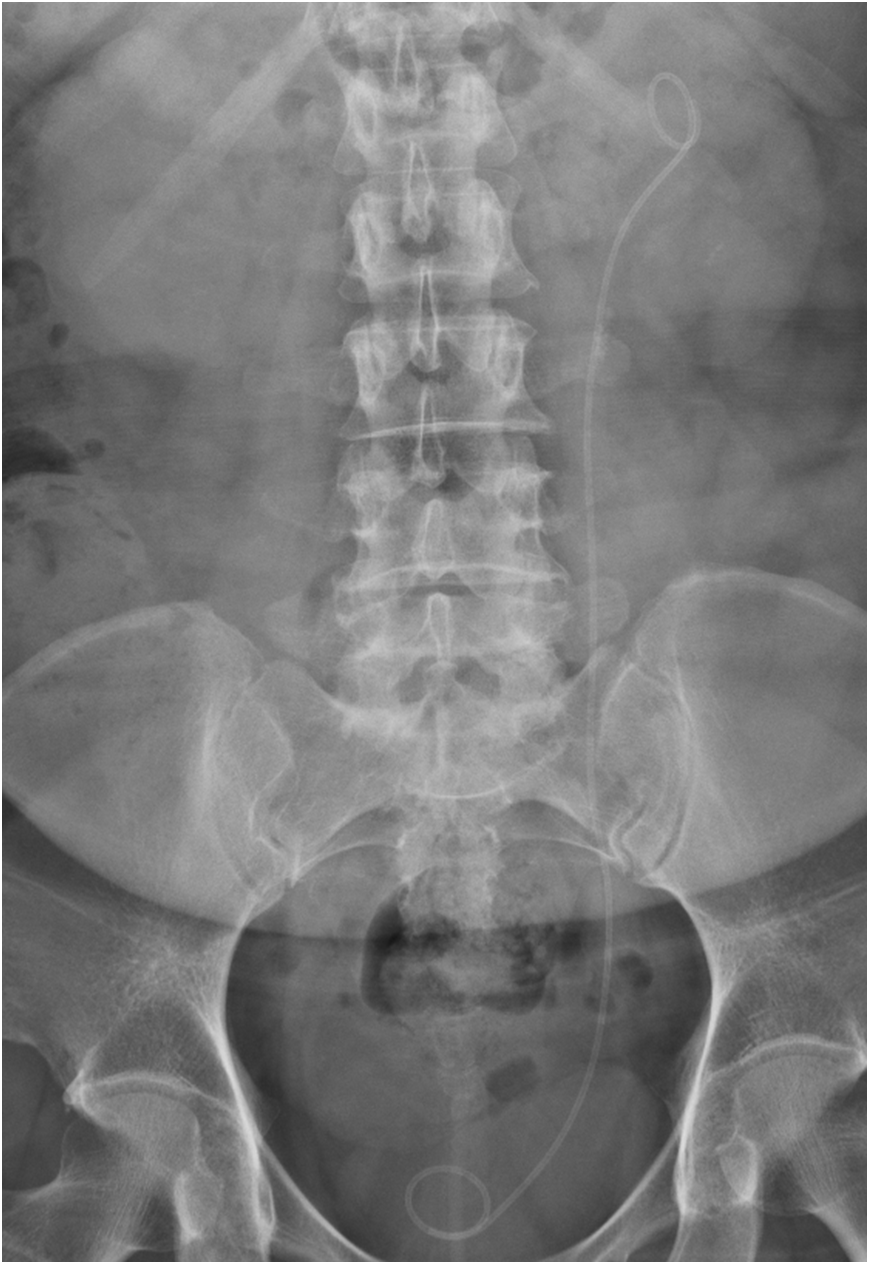

因病情需要留置较长期间(>3月),应定期进行腹部平片、尿常规及肾功能检查,密切关注DJ管的位置、感染及肾功能变化。

输尿管支架管,因为形似字母“J”,故又称为“DJ管”、“双J管”或“猪尾巴管”,它作为一种中空的管状支架,在泌尿系统中发挥着关键作用。

针对上尿路结石,输尿管DJ管已成为众多结石患者术后保护输尿管的一个重要“利器”。

输尿管DJ管主要运用于多种泌尿系统疾病患者,尤其是上尿路结石术后、非结石梗阻导致肾积水、输尿管息肉形成等情况的患者。